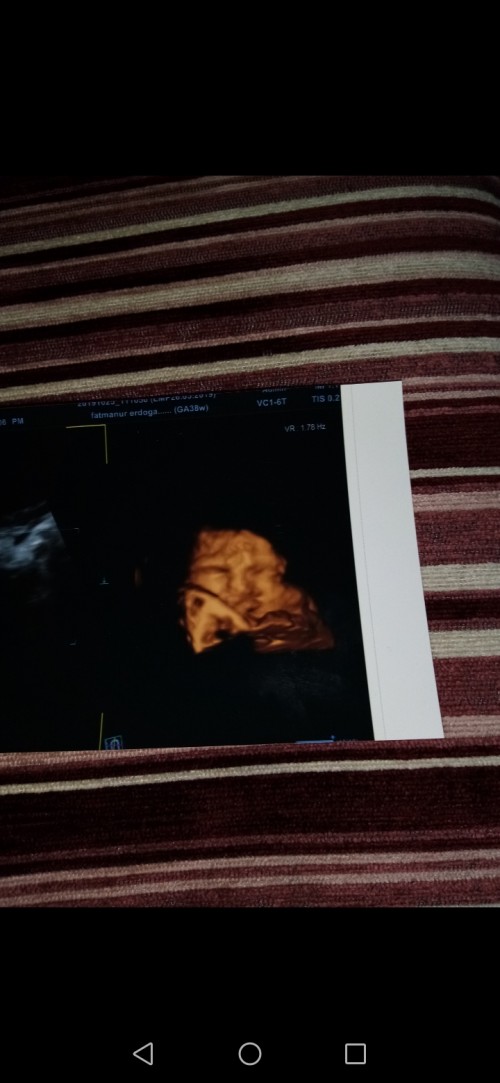

Geçen hafta 37 haftalıkken 2600 gr idi. Bugün kontrolde 3100 olmuş. 1 hafta geriden geliyordu üzülmüştüm biraz. Bugün mutlu oldum miniğim büyümüş. Ama 9 aydır poz vermiyor annesine artık doğunca görcez yüzünü :angel:<3

image